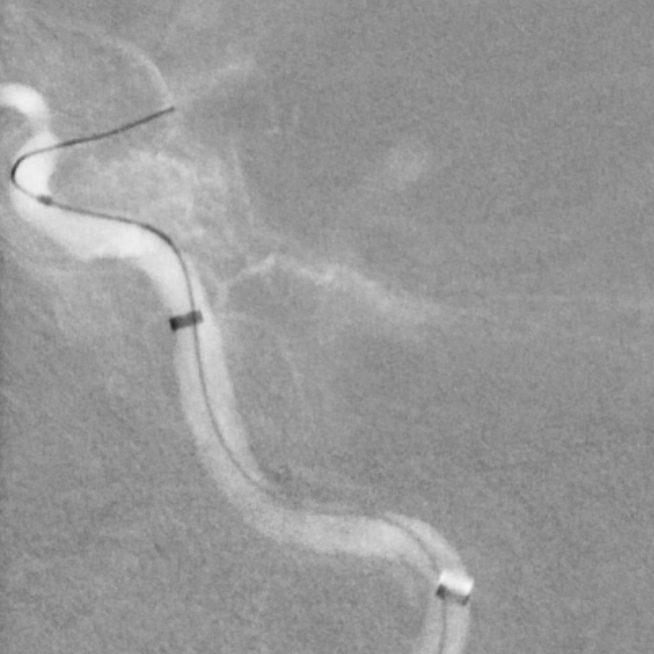

今日話題:頭暈、頭痛、頭懵又頭脹,是個什么梗?一、治療前1、頭暈頭懵頭脹3年,加重1年。2、走路下樓梯感覺無力發(fā)軟,喝水偶有嗆咳,記憶力減退2-3年3、高血壓10年,既往腦梗死病史4、2022年10月31,在院外行“球囊擴(kuò)張術(shù)”,頭暈沒有緩解。5、最近1年來,頭暈頭懵頭疼癥狀明顯,記憶力下降,一天到晚都在暈,休息后可以部分緩解,姿勢改變?nèi)菀最^暈,畏懼轉(zhuǎn)頭。6、2023年10月底外院復(fù)查造影,提示“左側(cè)頸內(nèi)動脈閉塞”。二、治療計劃1、開通閉塞的血管,消除頭痛、頭懵和頭脹2、1個月后二期消除頭暈三、治療過程成功開通閉塞的左側(cè)頸內(nèi)動脈顱內(nèi)段,消除左側(cè)腦部的低灌注三、小結(jié)頭暈頭懵又頭脹,可能不是一個病哦,需要進(jìn)一步查找病根~~~??